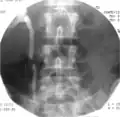

Матка с миомами до 36 недель. Матку сохранили благодаря ЭМА.